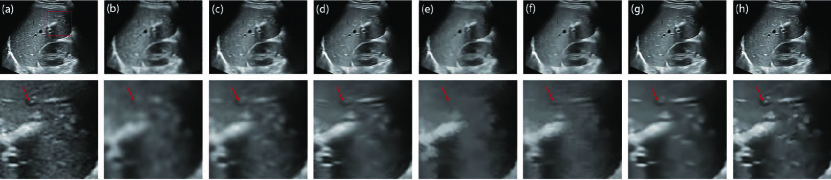

IV-C Application to ultrasound image segmentation

For validating the performance of our method, we apply each filter to breast ultrasound (BUS) image segmentation. BUS images are commonly used to differentiate between benign and malignant tumours, which can be characterized by their shapes or contours of segmented breast lesions [8]. We first despeckle ten breast ultrasound images with different lesions using different filters. A level-set method[70]444http://www.imagecomputing.org/~cmli/DRLSE/ is employed to segment the despeckled results. To validate the segmentation performance for all the ten images, we use the mean value of DSC metrics by averaging the metrics of ten segmentation results to evaluate each filter’s despeckling effect on the segmentation performance. Specifically, we first set the range of related parameters of level-set method, then choose the optimal parameters that achieve the highest scores of the mean DSC for the ten BUS segmentation results. Fig. 10 displays the BUS segmentation555The segmentation results of different filters on the ten images are attached in the supplemental file.: the green curves are the segmentation results of different filters and the yellow curve is the ground truth delineated by an expert; after the speckle reduction, each filter improves the performance of the segmentation result compared with the original BUS image. Among these filters, the segmentation result based on the PFDTV filter is closest to the ground truth. The filtered lesions via other filters are very blurry so that the segmentation method [70] is not able to accurately delineate the lesions from these despeckled images.

We adopt four evaluation metrics [71], including the dice similarity coefficient (DSC) [40], Jaccard similarity (JS) [72], Hausdorff distance (HD) and Hausdorff mean (HM) [73] to measure the segmentation accuracy. As simple spatial overlap indices and producibility validation metrics, DSC and JS measure the overlapping rate between the obtained segmentation region and the ground truth. As effective distance metrics between two finite point sets, HD and HM compute the distance of the contours between the obtained segmentation region and the ground truth. Hence, a better segmentation result should have higher DSC and JS, as well as lower HD and HM. Table III and Table IV list the mean and median values of DSC, JS, HD and HM for different segmentation results on ten despeckled BUS images, respectively. Obviously, PFDTV achieves the largest DSC and JS values, as well as the smallest HD and HM values, which indicate that PFDTV achieves better segmentation performance compared with other filters.